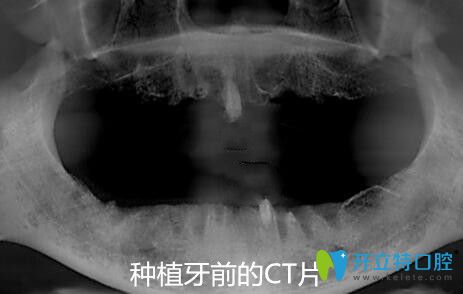

從面診到拍CT片、身體的多種常規(guī)檢查等,一樣不漏;統(tǒng)統(tǒng)做完后才制定修復(fù)方案。方醫(yī)生說從各種檢查情況來看,我比較適合做全口ALL-ON-4種植牙,這樣不僅省錢,手術(shù)速度快、創(chuàng)傷也很小。

下面是我做種植牙前的照片▼,看上去像五六十歲的樣子,其實(shí)才40歲;全口牙缺失不僅耽誤吃東西,而且讓整個(gè)人都很顯老~~~